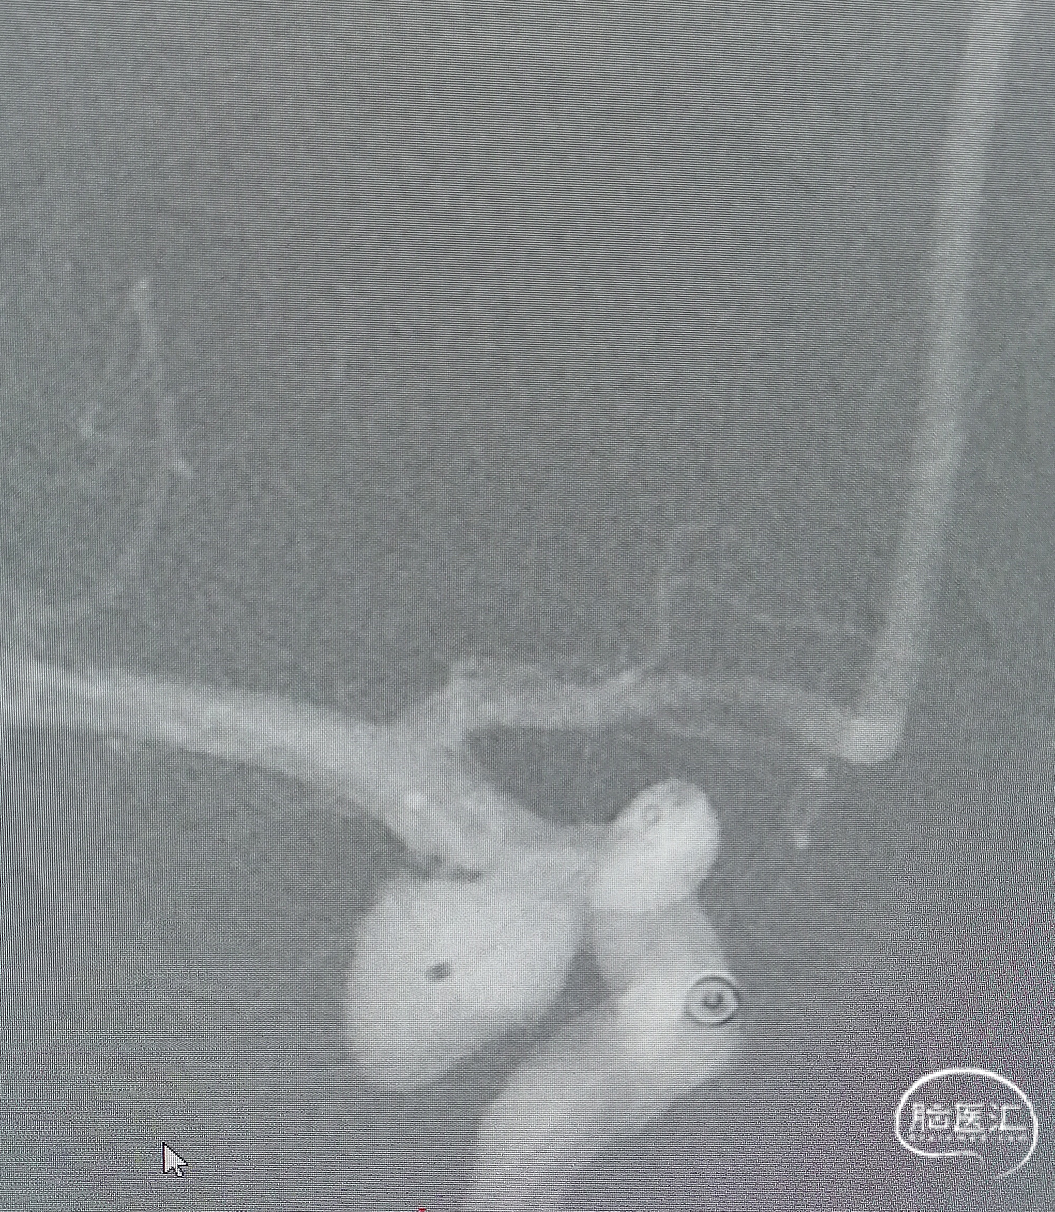

将泰杰TJMC18 Plus支架微导管越过瘤颈远端至少5cm,然后将预期血管内直径/长度为4.0mm*24mm的Nuva®密网支架输送到位,完成远端定位后,推拉结合缓慢半释放Nuva®密网支架。

术后即刻造影可见支架内血流通畅,动脉瘤内可见明显造影剂滞留,远端分支显影无缺失。

1.本病例为颈内动脉后交通段动脉瘤,是动脉瘤高发部位之一,瘤颈较宽,选择血管内治疗有助于手术顺利开展。Nuva®血流导向密网支架,操作简便,术中释放顺利,充分覆盖动脉瘤瘤颈口,血流导向作用显著,有利于患者良好预后。

2.Nuva®密网支架输送系统的释放-回收段显影设计,术中可准确快速指示出释放-可回收区域,区间显影设计极大地方便了术中的操作,有助于支架的成功释放。

3.Nuva®密网支架具有较好的柔顺性,释放于迂曲的血管中,可以很好地顺应血管形态,术中打开顺畅,贴壁良好,径向支撑力适中,推挤过程也不易折弯变形;支架整体显影设计,透视效果优异,术中很容易观察支架的打开、走形及贴壁情况。